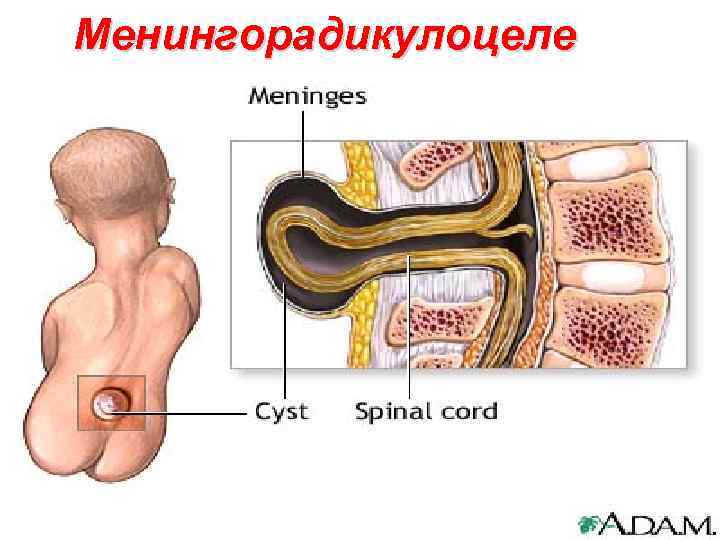

Менингорадикулоцеле 112